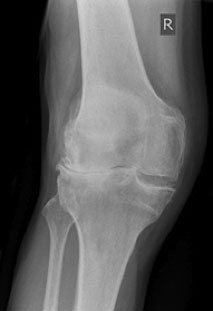

Figure 1: X-ray of the right knee showing the typical features of osteoarthritis, joint space narrowing and spurs of bone

There is no blood test to diagnose osteoarthritis. The diagnosis is readily made on symptoms and clinical signs on examination. X-rays are used widely to confirm the diagnosis. An x-ray is likely to show narrowing of the space between the bones where the gristle has worn and also spurs of bone.